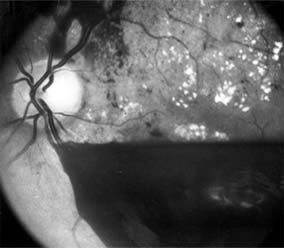

The fragile new vessels proliferate onto the posterior face of the vitreous and become elevated once the vitreous starts to contract away from the retina. If the vessels bleed (Figure 10-26), massive vitreous hemorrhage may cause sudden visual loss. Eyes in which posterior vitreous detachment is complete are at less risk of developing neovascularization and vitreous hemorrhage. In eyes with proliferative diabetic retinopathy and persistent vitreoretinal adhesions, elevated neovascular fronds may undergo fibrous change and form tight fibrovascular bands that tug on the retina and exert continued vitreous contraction. This can cause either a progressive traction retinal detachment or, if a retinal tear is produced, rhegmatogenous retinal detachment. The retinal detachment may be heralded or concealed by vitreous hemorrhage. When vitreous contraction is complete in these eyes, proliferative retinopathy tends to enter the burned-out or "involutional" stage.

Figure 10-26

Figure 10-26: Proliferative diabetic retinopathy with preretinal hemorrhage obscuring the inferior macula. Macular exudate, microaneurysms, and intraretinal hemorrhages are also present.